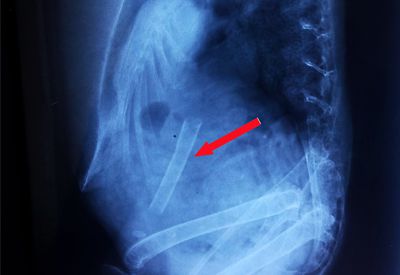

Fremdkörper verschluckt - Ein häufiges Problem in der Papageienhaltung